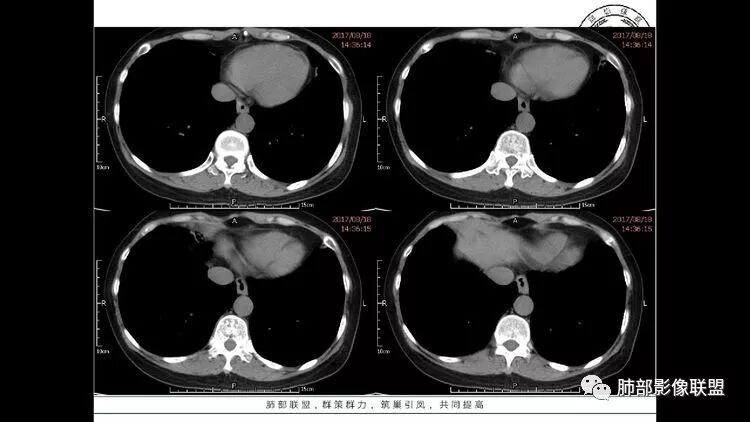

胸CT:1.双肺多发囊性变,以中下肺为主,病变边缘可见肺动脉,部分囊内可见分隔及肺动脉,双下部分肺野周围可见小叶中心结节及树丫征。

3.纵隔淋巴结肿大?,以主动脉弓为界向上向下增大。

中年女性,因“角膜炎”入院,自用眼液2年,(眼干?)肺部:双肺多发类圆形薄壁气囊+实性结节+GGO,下肺分布为主,纵隔淋巴结肿大,考虑淋巴系统增殖,LIP可能性大,可能继发于干燥综合症;左肺下叶的混合磨玻璃结节形迹可疑,边界清晰,内部疑似空泡,扩张扭曲支气管,极像肺癌,伴双肺转移?待排吧

55岁女性,右眼红痛视力下降1天。既往有类风湿病史。两肺多发大小不等囊及结节,左下肺磨玻璃结节样病灶,纵隔占位。一元解释不了这么多不同病灶,二元甚至三元。纵隔恶性肿瘤并肺内转移?左下肺腺癌并肺内纵隔淋巴结转移?LIP?

多发气囊,气囊内可见血管进入,因患者眼干伴类风湿,可能有干燥综合征,那LIP可能性大。因为不是育龄期发病,可排除LAM。患者左纵膈淋巴结肿大,且有融合趋势,结合左下肺病灶,考虑合并恶性肿瘤,淋巴瘤?鉴别结节病

左肺下叶混杂密度病灶,其内可见空泡,周围ggo清楚,考虑浸润性腺癌。双肺散在多发薄壁囊腔和实性结节,以胸膜下及血管旁分布位于,气囊可见血管贴边征,双肺小叶间隔及中央间质增厚,局部可见磨玻璃影及树芽征,纵隔内淋巴结肿大,考虑LIP

综上,考虑左下肺浸润性腺癌+LIP

双肺多发大小不等囊腔,可见薄壁,部分囊腔内可见血管影,伴双肺多发结节,结合患者眼病及类风湿病史,考虑LIP可能大。另左肺下叶磨玻璃结节,边界清晰,内可见空泡,伴纵膈多发肿大淋巴结,不除外浸润性腺癌可能。